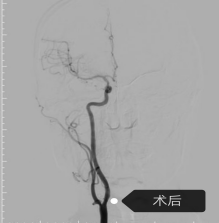

手术当日,神经内科介入团队娴熟操作介入设备,导丝、导管、支架系统操作顺利送达指定部位,成功将支架输送至狭窄部位并精准释放,瞬间打通了狭窄严重的血管,恢复了大脑的正常供血,整台手术流畅顺利,采用局部麻醉,患者全程清醒,无身体不适反应。

术后患者便可下床上厕所,行动自如,日常活动恢复正常,术前症状消失,脸上露出了久违的笑容。对于如此迅速的重获健康,患者及家属激动不已,特意将两面满载感激之情的锦旗送到科室,盛赞神经内科团队“医德高尚,仁心仁术”。